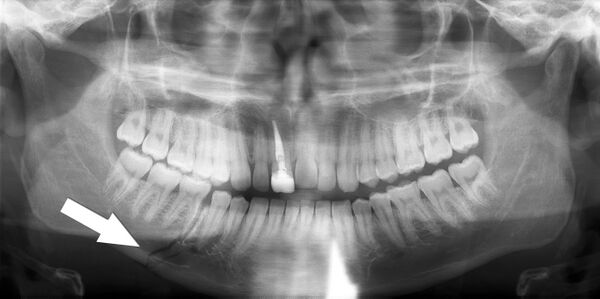

Ортопантомография (от греч.: orthos — прямой, правильный, pan — всё, tomos — ломоть, отрезанный кусок и grapho — писать, рисовать) — особый вид рентгеновской съёмки костей лицевого скелета, при котором они «развёртываются» в одну плоскость[1]. Другими словами рентгенологическое исследование в стоматологии, челюстно-лицевой хирургии, косметологии, позволяющее получать развёрнутое изображение всех зубов с челюстями, прилежащими отделами лицевого скелета. Является первичным рентгенологическим исследованием[2].

Галерея